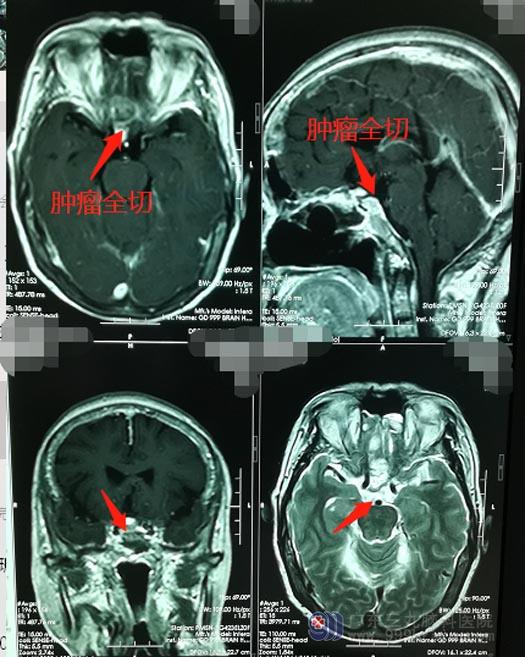

因为鞍结节脑膜瘤是处在脑子的正中央,手术难度相对较大,医院副院长、神经外五科主任鲁明带领团队为钟阿姨选择了全麻下行内镜“经鼻蝶鞍结节脑膜瘤切除术”,手术过程中保护好垂体功能,将肿瘤顺利全切。

术后,钟阿姨神志清醒,视力视野正常, MRI显示鞍结节病灶已切除,无残留。